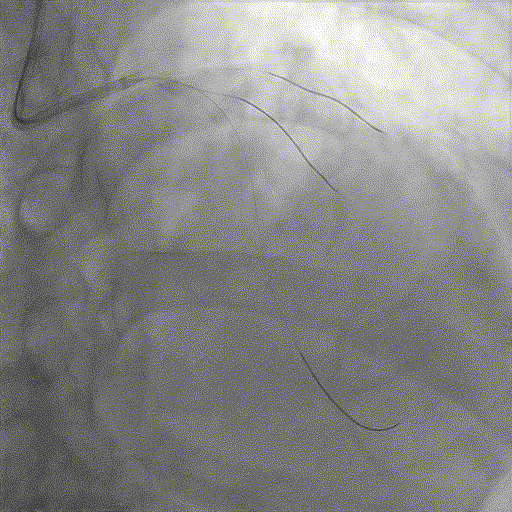

手术过程

导丝到位

当指引导管冠脉开口到位后,选择三根对应导丝分别送入LCX、OM1、OM2远端。

OM2优先处理:

球囊预扩

当导丝通过病变后其他器械无法通过病变,此时选择不同尺寸的小球囊逐级预扩张病变,复查造影狭窄减轻不明显。为了解血管真实情况,遂启用IVUS检查。

术前腔内影像学IVUS指导

IVUS提示血管可见钙化明显,为360°环形钙化。遂考虑启动IVL治疗。

冲击波球囊治疗

2.5*12mm@4atm 冠脉血管内冲击波导管反复进行4个周期治疗,复查造影提示狭窄减轻。

支架植入并后扩

于OM2-LCX远端植入一枚药物洗脱支架,经非顺应性球囊后扩张支架,复查造影提示支架贴壁良好,未见夹层、血肿。